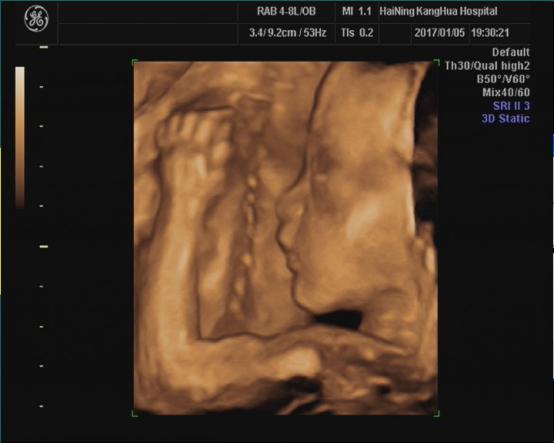

海宁康华医院“胎儿三维彩超检查”,为您创造“透视”条件!

胎儿三维超声检查最佳时间:

22—24周(备注:双胎不做三维超声检查)